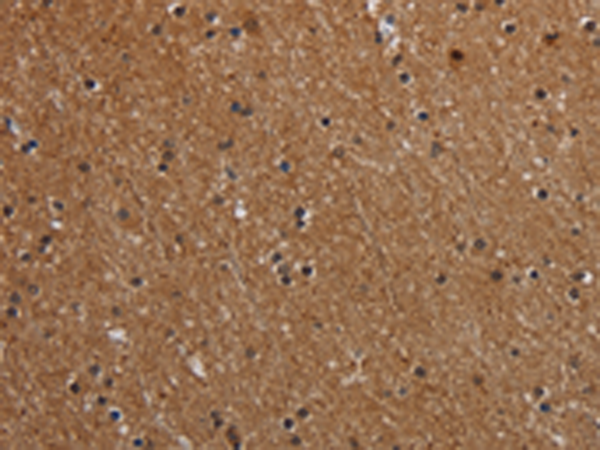

分类: 科研抗体货号: P05123别名: FDP; MIAL1应用: IHC反应种属: Human, Mouse